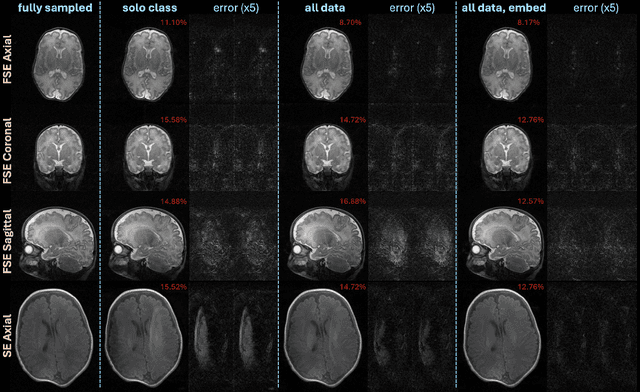

Abstract:Purpose: Magnetic Resonance Imaging (MRI) enables non-invasive assessment of brain abnormalities during early life development. Permanent magnet scanners operating in the neonatal intensive care unit (NICU) facilitate MRI of sick infants, but have long scan times due to lower signal-to-noise ratios (SNR) and limited receive coils. This work accelerates in-NICU MRI with diffusion probabilistic generative models by developing a training pipeline accounting for these challenges. Methods: We establish a novel training dataset of clinical, 1 Tesla neonatal MR images in collaboration with Aspect Imaging and Sha'are Zedek Medical Center. We propose a pipeline to handle the low quantity and SNR of our real-world dataset (1) modifying existing network architectures to support varying resolutions; (2) training a single model on all data with learned class embedding vectors; (3) applying self-supervised denoising before training; and (4) reconstructing by averaging posterior samples. Retrospective under-sampling experiments, accounting for signal decay, evaluated each item of our proposed methodology. A clinical reader study with practicing pediatric neuroradiologists evaluated our proposed images reconstructed from 1.5x under-sampled data. Results: Combining all data, denoising pre-training, and averaging posterior samples yields quantitative improvements in reconstruction. The generative model decouples the learned prior from the measurement model and functions at two acceleration rates without re-training. The reader study suggests that proposed images reconstructed from approximately 1.5x under-sampled data are adequate for clinical use. Conclusion: Diffusion probabilistic generative models applied with the proposed pipeline to handle challenging real-world datasets could reduce scan time of in-NICU neonatal MRI.